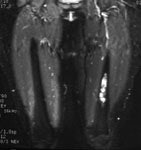

Ewings sarcoma of the pelvis: The bone scan demonstrates extensive, intense tracer uptake involving the left iliac wing, extending into the ischium and left sacrum. CT scan revealed a mixed, but predominantly sclerotic lesion involving the bone with an associated soft tissue mass. Note that the sacrum fails to demonstrate a CT abnormality. The T2 weighted images from the patients MR exam more clearly defines the lesion. Sacral involvement is clearly evident (white arrows) and there is also a large soft tissue component. |